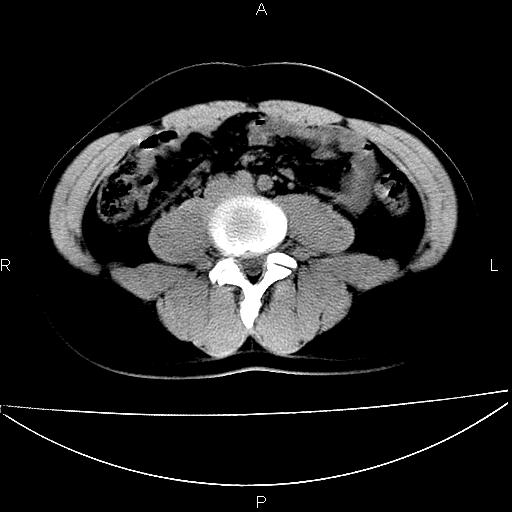

男 25岁 自述 尿频尿急,排尿困难20多天.无腰痛, b超说左肾盂轻度积水,左输尿管上端扩张.未见结石影. ct我看双侧肾盂轻度积水,双输尿管上端都扩张,大家看看能看见结石吗?

双肾轻度积水,双侧输尿管上段扩张(原因待查)。

双输尿管扩张下端未见高密度结石和输尿管晕轮征,不好说是结石.增强后如何?

双肾盂及双输尿上段轻度积水,双输尿管未见明显结石影。